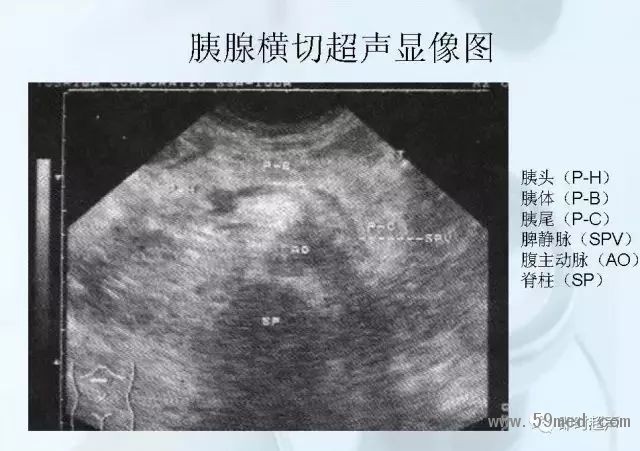

新聞中心 收藏!正常B超解剖圖譜,超實用!